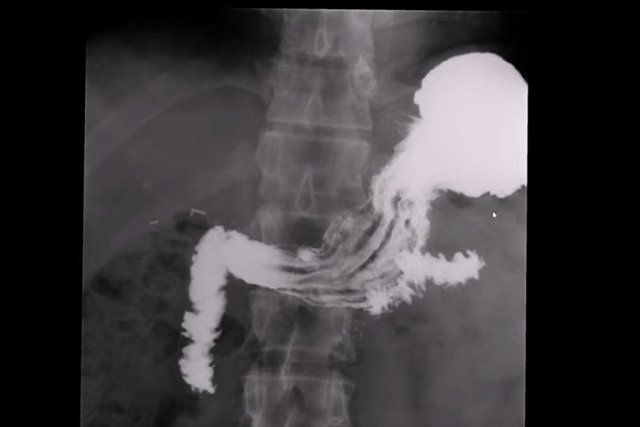

Диагностический центр в Санкт-Петербурге использовал для исследований поддельный контраст на основе бария, установили следователи. Главврач городского консультативно-диагностического центра №1 допустил использование поддельного препарата для гастроскопии.

В Петербурге задержан главный врач Городского консультативно-диагностического центра (ГКДЦ) №1, где после обследования желудка скончались пациенты. "Задержан, решается вопрос об избрании меры пресечения", - сообщил "Интерфаксу" информированный источник.

В Петербурге в диагностическом центре пациенты погибли после обследования желудка. На утро 27 января погибли трое, еще трое находятся в реанимации, сообщил "Интерфаксу" информированный источник.